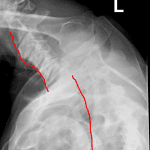

- Severe anterolisthesis at the cervicothoracic junction, best appreciated on the swimmer’s view

- Severe anterolisthesis at the cervicothoracic junction

Severe anterolisthesis at the cervicothoracic junction, best appreciated on the swimmer’s view. Recommend urgent surgical consultation and C spine CT for further evaluation.

No evidence of acute displaced fracture, though evaluation of the lower cervical spine is limited by overlying soft tissues.

Advanced multilevel cervical spondylosis with disc space narrowing and endplate sclerosis/spurring most advanced from C4-C5 through C6-C7.

Bilateral carotid artery calcification.